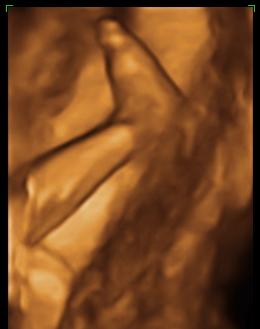

babalak a 22. héten

Dávid